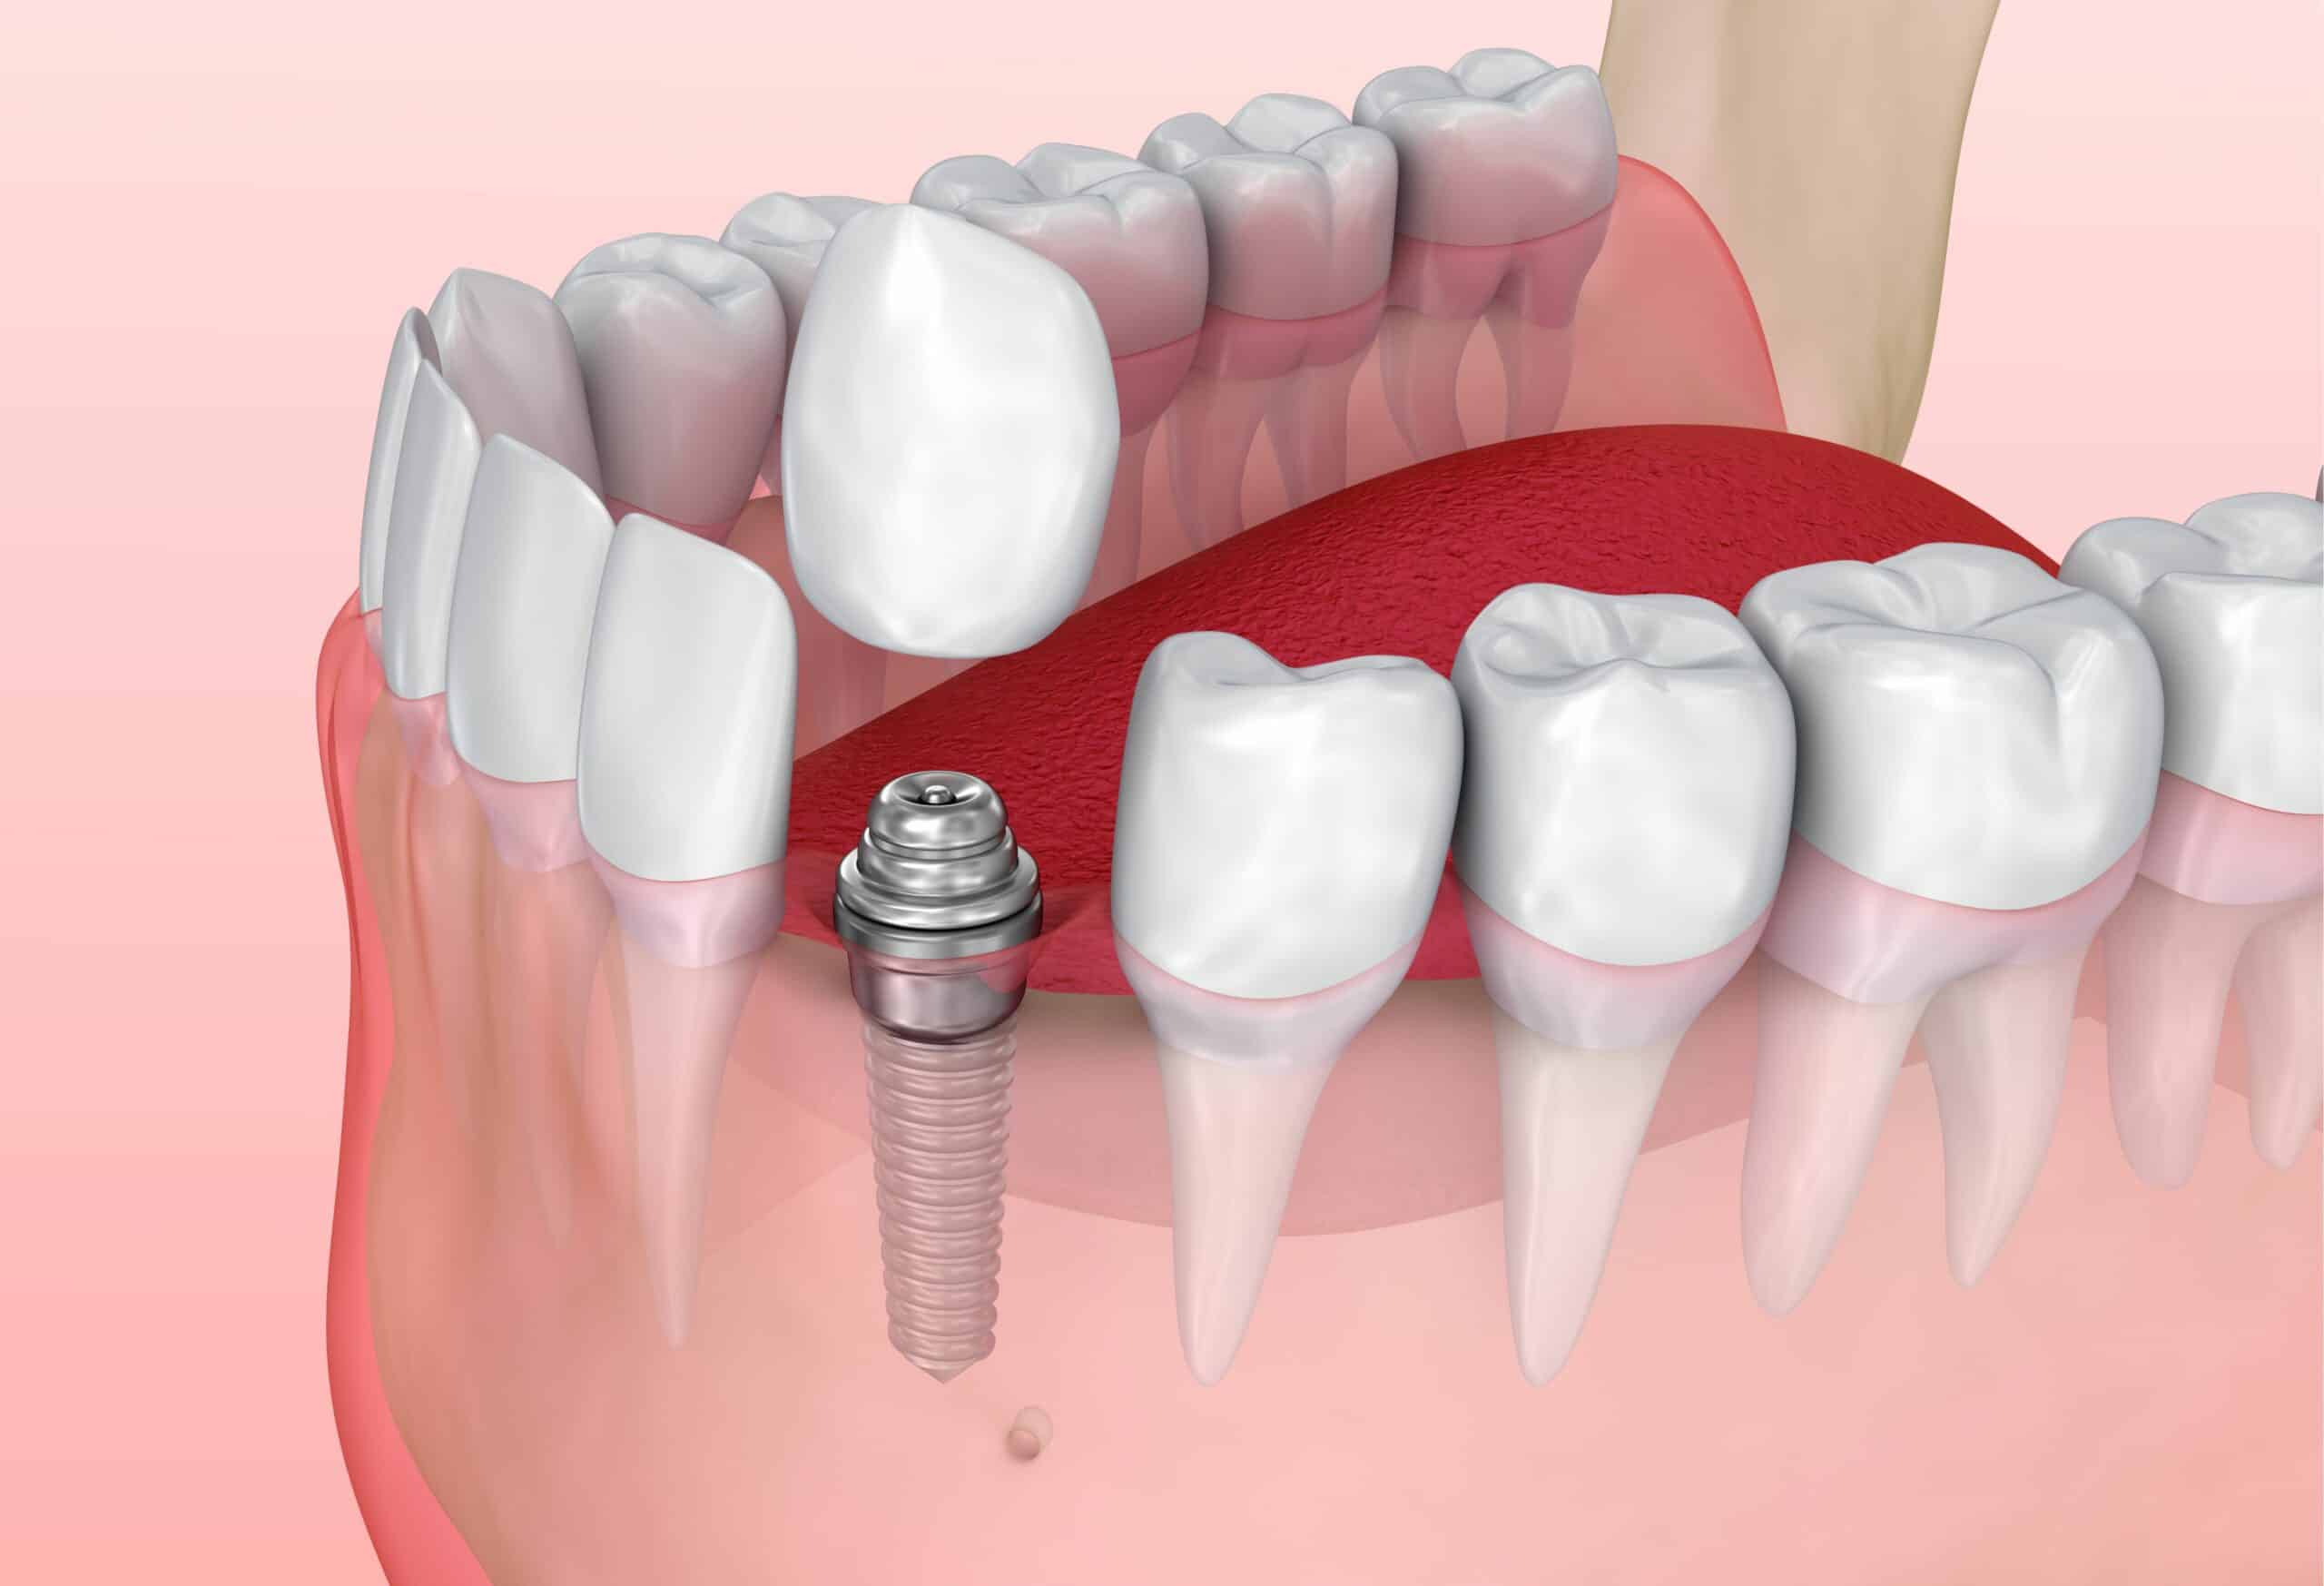

Современная стоматология: Железные зубные импланты